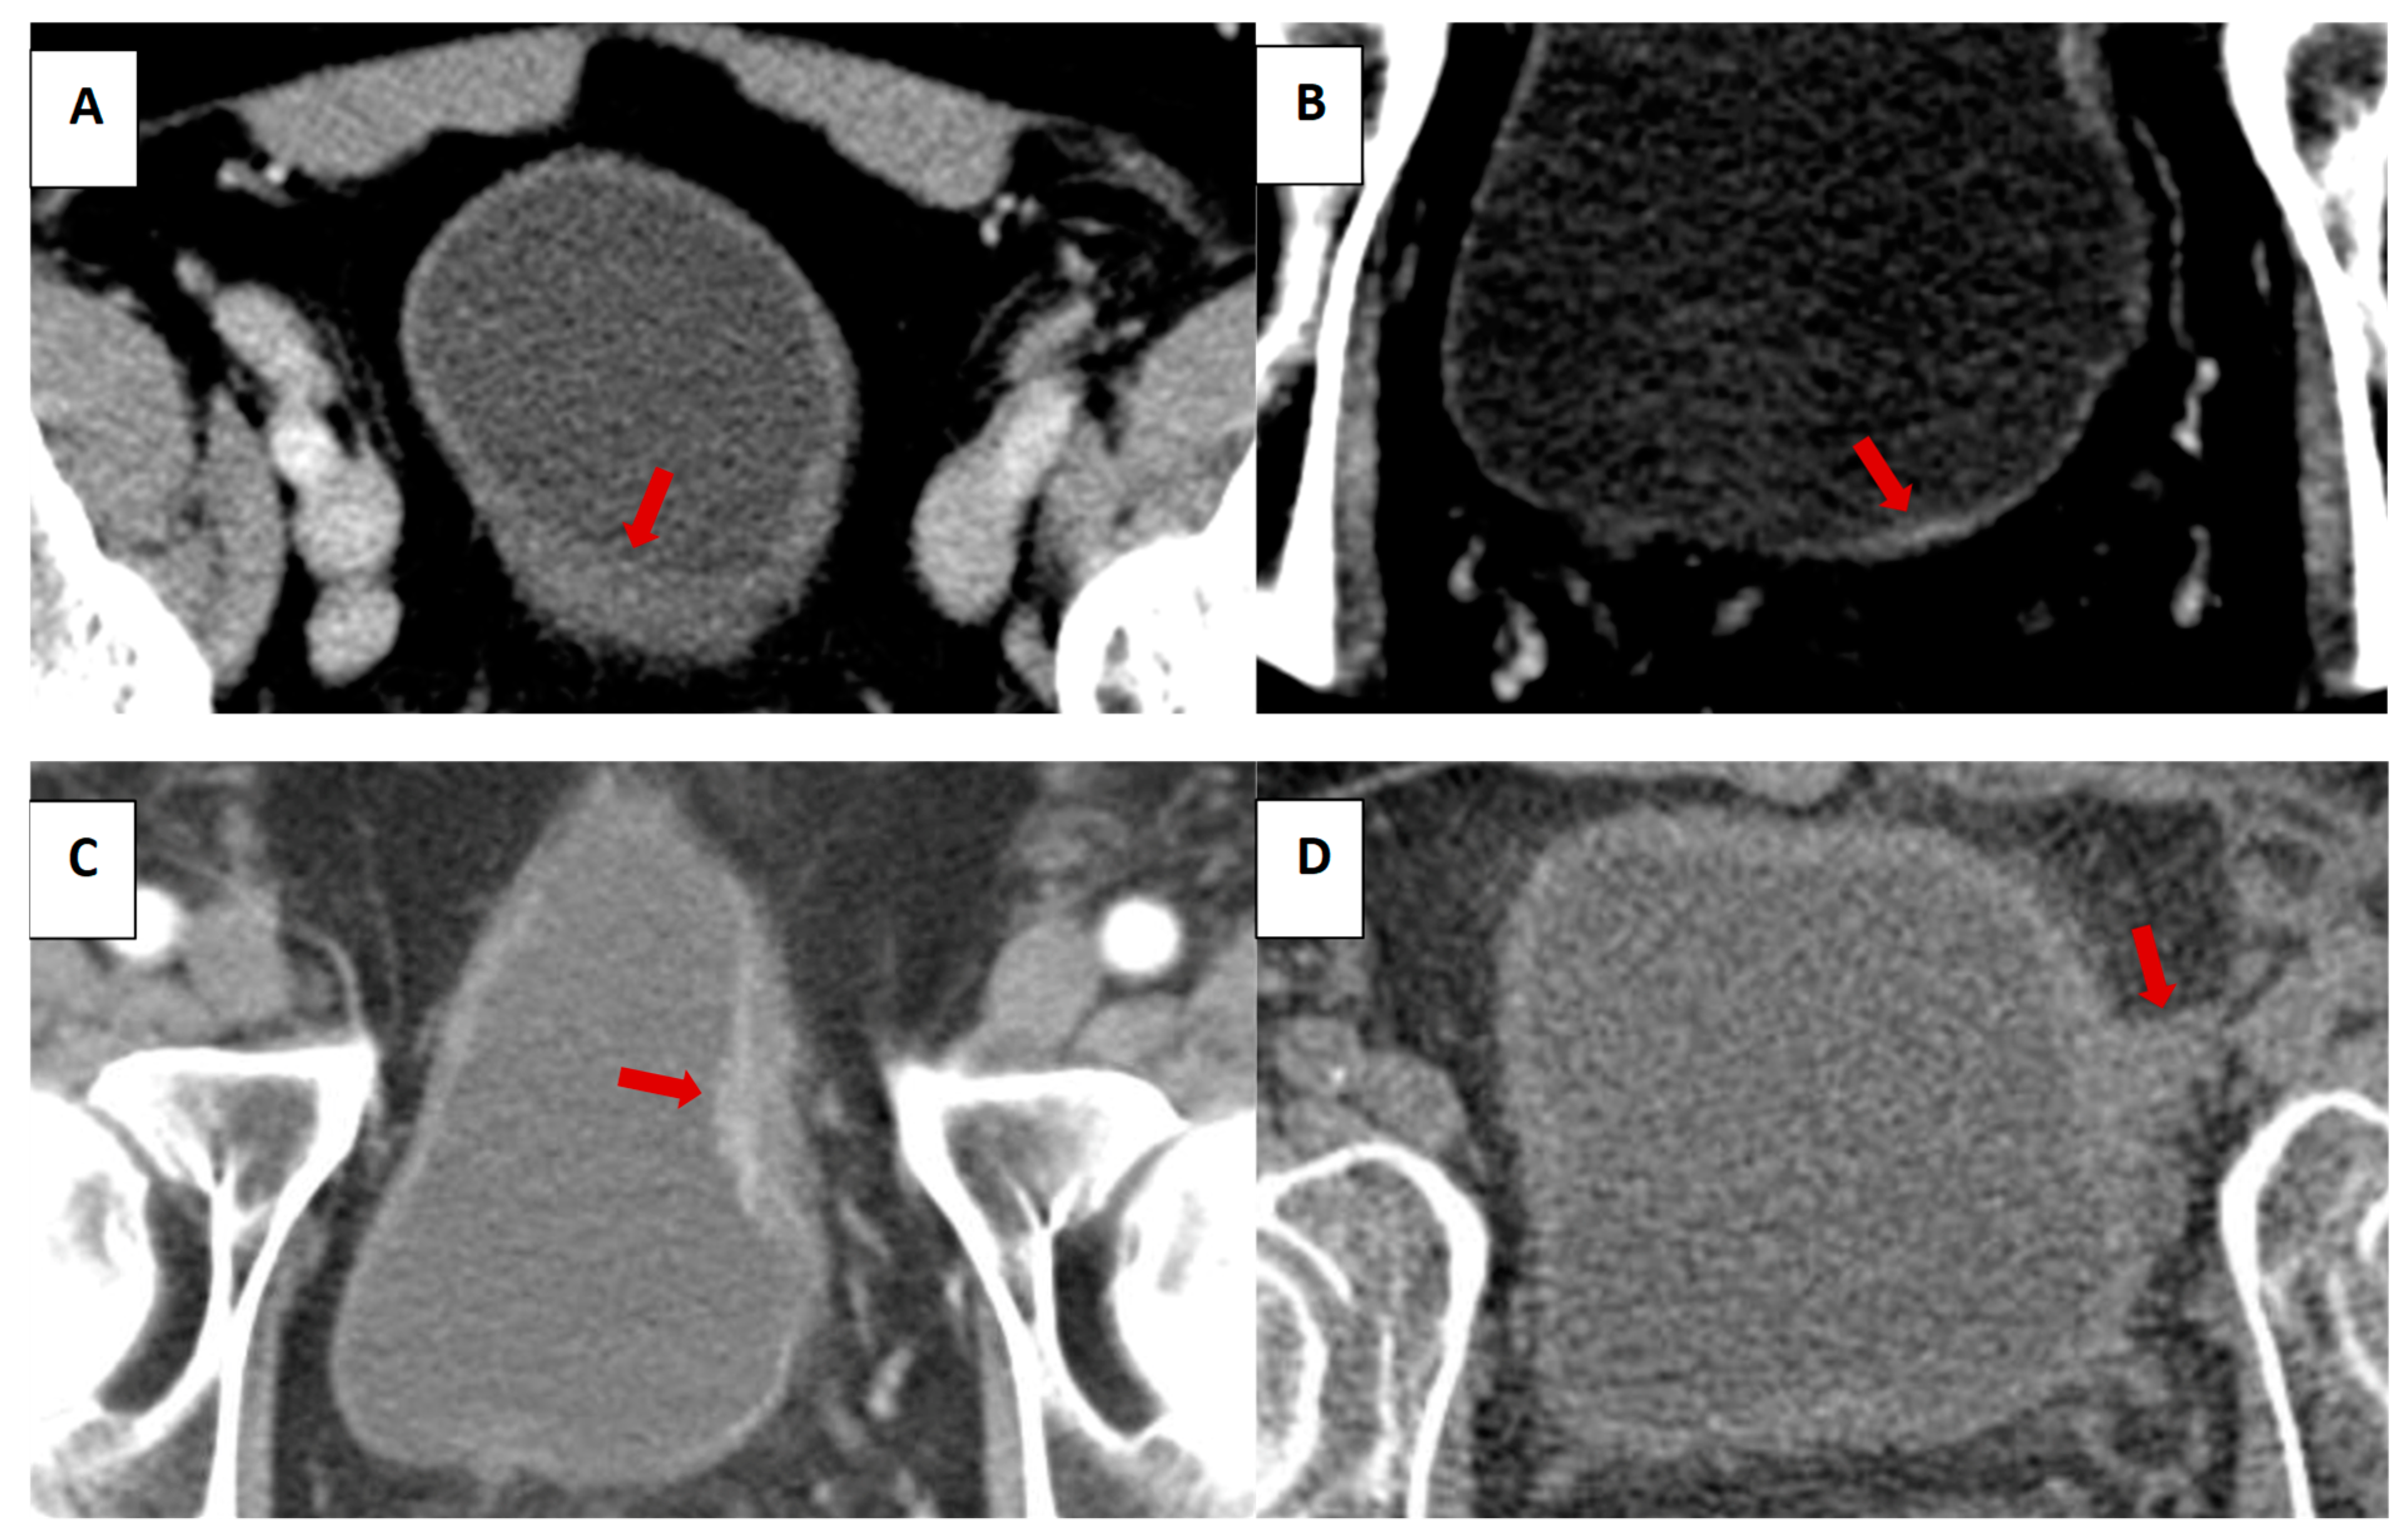

We assessed the following features on prior CT: IV contrast phases in the pelvis, bladder distention (volume calculated using the prolate ellipsoid method, (length x height x width x 0.57) [34], focal wall thickening (presence and measurement), focal wall enhancement (presence), and the presence and long-axis measurements of the following: intraluminal mass, intramural mass, and extramural mass of the bladder (illustrated in Figure 1). Assessment was made by one of two board-eligible body imaging fellows and confirmed by a board-certified radiologist with over 10 years’ experience. Readers were aware that patients subsequently developed bladder cancer, but were blinded to the date of pathologic diagnosis.

Figure 1.

Illustrative examples of focal wall thickening (A), focal wall enhancement (B), intraluminal mass (C), and extramural mass (D). Red arrows to indicate bladder lesions.